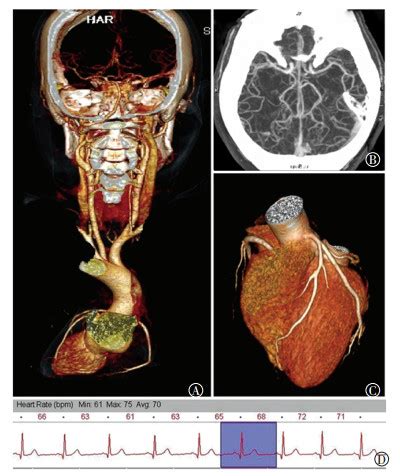

头颅检查,CT、核磁共振哪个好?贵的会更准吗?一般我们不会说哪个贵就哪个好 。对于头颅来说,MRI的整体诊断准确率和对治疗的评估方面要优于CT 。至于问题到提到的准字,我想回答起来就没那么容易了 。所谓精准医疗是近几年才提出的概念吧,要想精准医疗,确实得先检查的精准,而以CT和MRI为优秀代表的医学影像学确实是精准医疗的基石,没有精准的检查,何来精准的治疗?我们来说说对于头颅的病变,哪些病变核磁会“更准”一些,而哪一小部分需要做CT呢?先说说常见的中风,多见于两种情况,一种是脑出血,一种是脑血栓 。

这两种疾病在临床的表现几乎一样,都是“中风”,但治疗却恰好相反,如果是出血,要止血,如果是血栓,要溶栓 。怎么办呢?现在临床急诊,多做CT解决,因为CT上急性脑出血是白色的,很容易识别 。而如果没有出血,就考虑中风的原因是脑梗塞了 。脑梗塞怎么确诊?24小时内的梗塞很可能在CT上不好区分(有些能表现出来),但核磁能把这个时间窗提前到几个小时以内,所以诊断脑梗塞很显然是核磁更准 。

出血呢?出血在核磁上表现的很复杂,没有经验,甚至有经验的大夫有时候也容易被搞晕 。这也就是为什么有时候做了核磁还要病人再做一次CT的原因之一 。急诊外伤患者,通常优选选择CT 。因为更便捷,而且对于骨折,CT很优厚优势 。再看看脑肿瘤、脑炎、脑白质病等脑内病变,这些病变通常来说核磁优于CT,因为核磁的序列更多,除了解剖结构,甚至还能反映其代谢情况(DWI,波谱),对于疾病诊断,手术或用药后疗效如何等作出更好的评价 。

但对于其中某些个别病变,有时候是需要CT辅助诊断的,比如某些含钙化的疾病等,需要具体问题具体分析 。还有,假如病人因种种原因,无法进行核磁检查,那就只能做CT了 。其他一些部位,比如垂体,虽然不是脑子病变,也属于颅内 。通常核磁对垂体病变更好,但在某些情况下,比如要术前明确局部骨质情况,或者无法做核磁的时候,也可能做CT 。